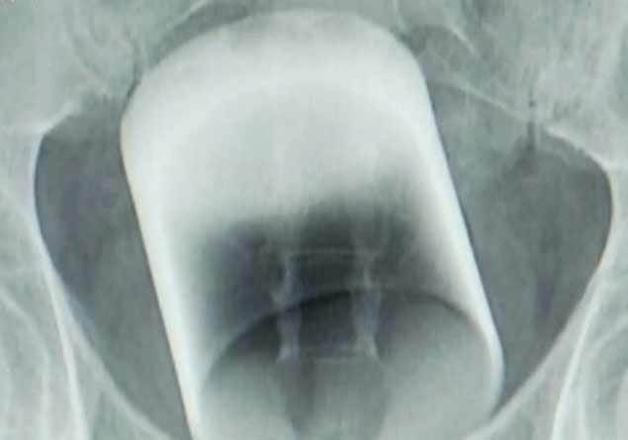

Çin'de akıllara durgunluk veren bir olay yaşandı. Tuvalete çıkma sorunu ve tıkanma şikayeti ile hastaneye başvuran bir kişinin makatında çekilen röntgen sonucu 8 santimetrelik bardak olduğu ortaya çıktı.

Tuvalete çıkma sorunu ve tıkanma şikayeti ile hastaneye başvuran bir kişinin makatında çekilen röntgen sonucu 8 santimetrelik bardak olduğu ortaya çıktı.

Çin'de röntgen filmi çektiren bir kişinin makatında 8 santimetre uzunluğunda bardak tespit edildi. Hasta, bardağın makatına nasıl girdiği konusunda açıklamaya yapmaktan kaçındı. Başarılı bir operasyon geçiren hastanın makatından 8 santimetrelik bardak kırılmadan çıkarıldı. Çin'in Guangzhou kentinde yaşayan ve evli olduğu öğrenilen kişi hastaneye dayanılmaz ağrı şikayeti ile geldi.

Sabahın erken saatlerinde hastaneye gelen kişi ağrısı sebebiyle çığlıklar atıyordu. Ağrının sebebini öğrenmek için doktorlar derhal adamın röntgen filmini çekti. Röntgen filminde makatta bir bardak olduğu görüldü ve bardağın kaslara aşırı baskı uyguladığı için acı ve ağrıya sebep olduğu anlaşıldı.